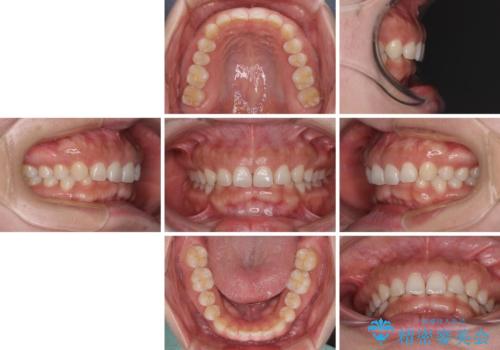

【モニター】ディープバイトを治す ワイヤー装置による矯正治療

- 顎が疲れるほどのディープバイトを気にして来院された患者様です。

手前に傾斜している奥歯を直立させながら、歯列全体の平面を均一に整えることでディープバイトを改善していくこととしました。

ディープバイトは咬合力が強いことが特徴であり、より良い仕上がりとするために、臼歯部のコントロールを行いやすいワイヤー装置を用いて矯正治療を行うこととしました。